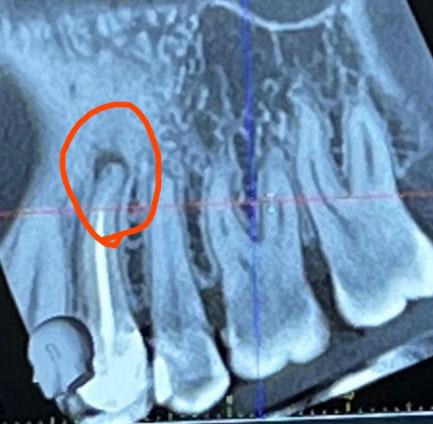

This CBCT image shows the anterior maxillary region with multiple natural teeth. A well-defined radiolucent lesion is visible at the root apex of a previously treated tooth (circled area), indicating a persistent apical infection. Surrounding bone shows early structural changes.

Clear apical radiolucency at root tip